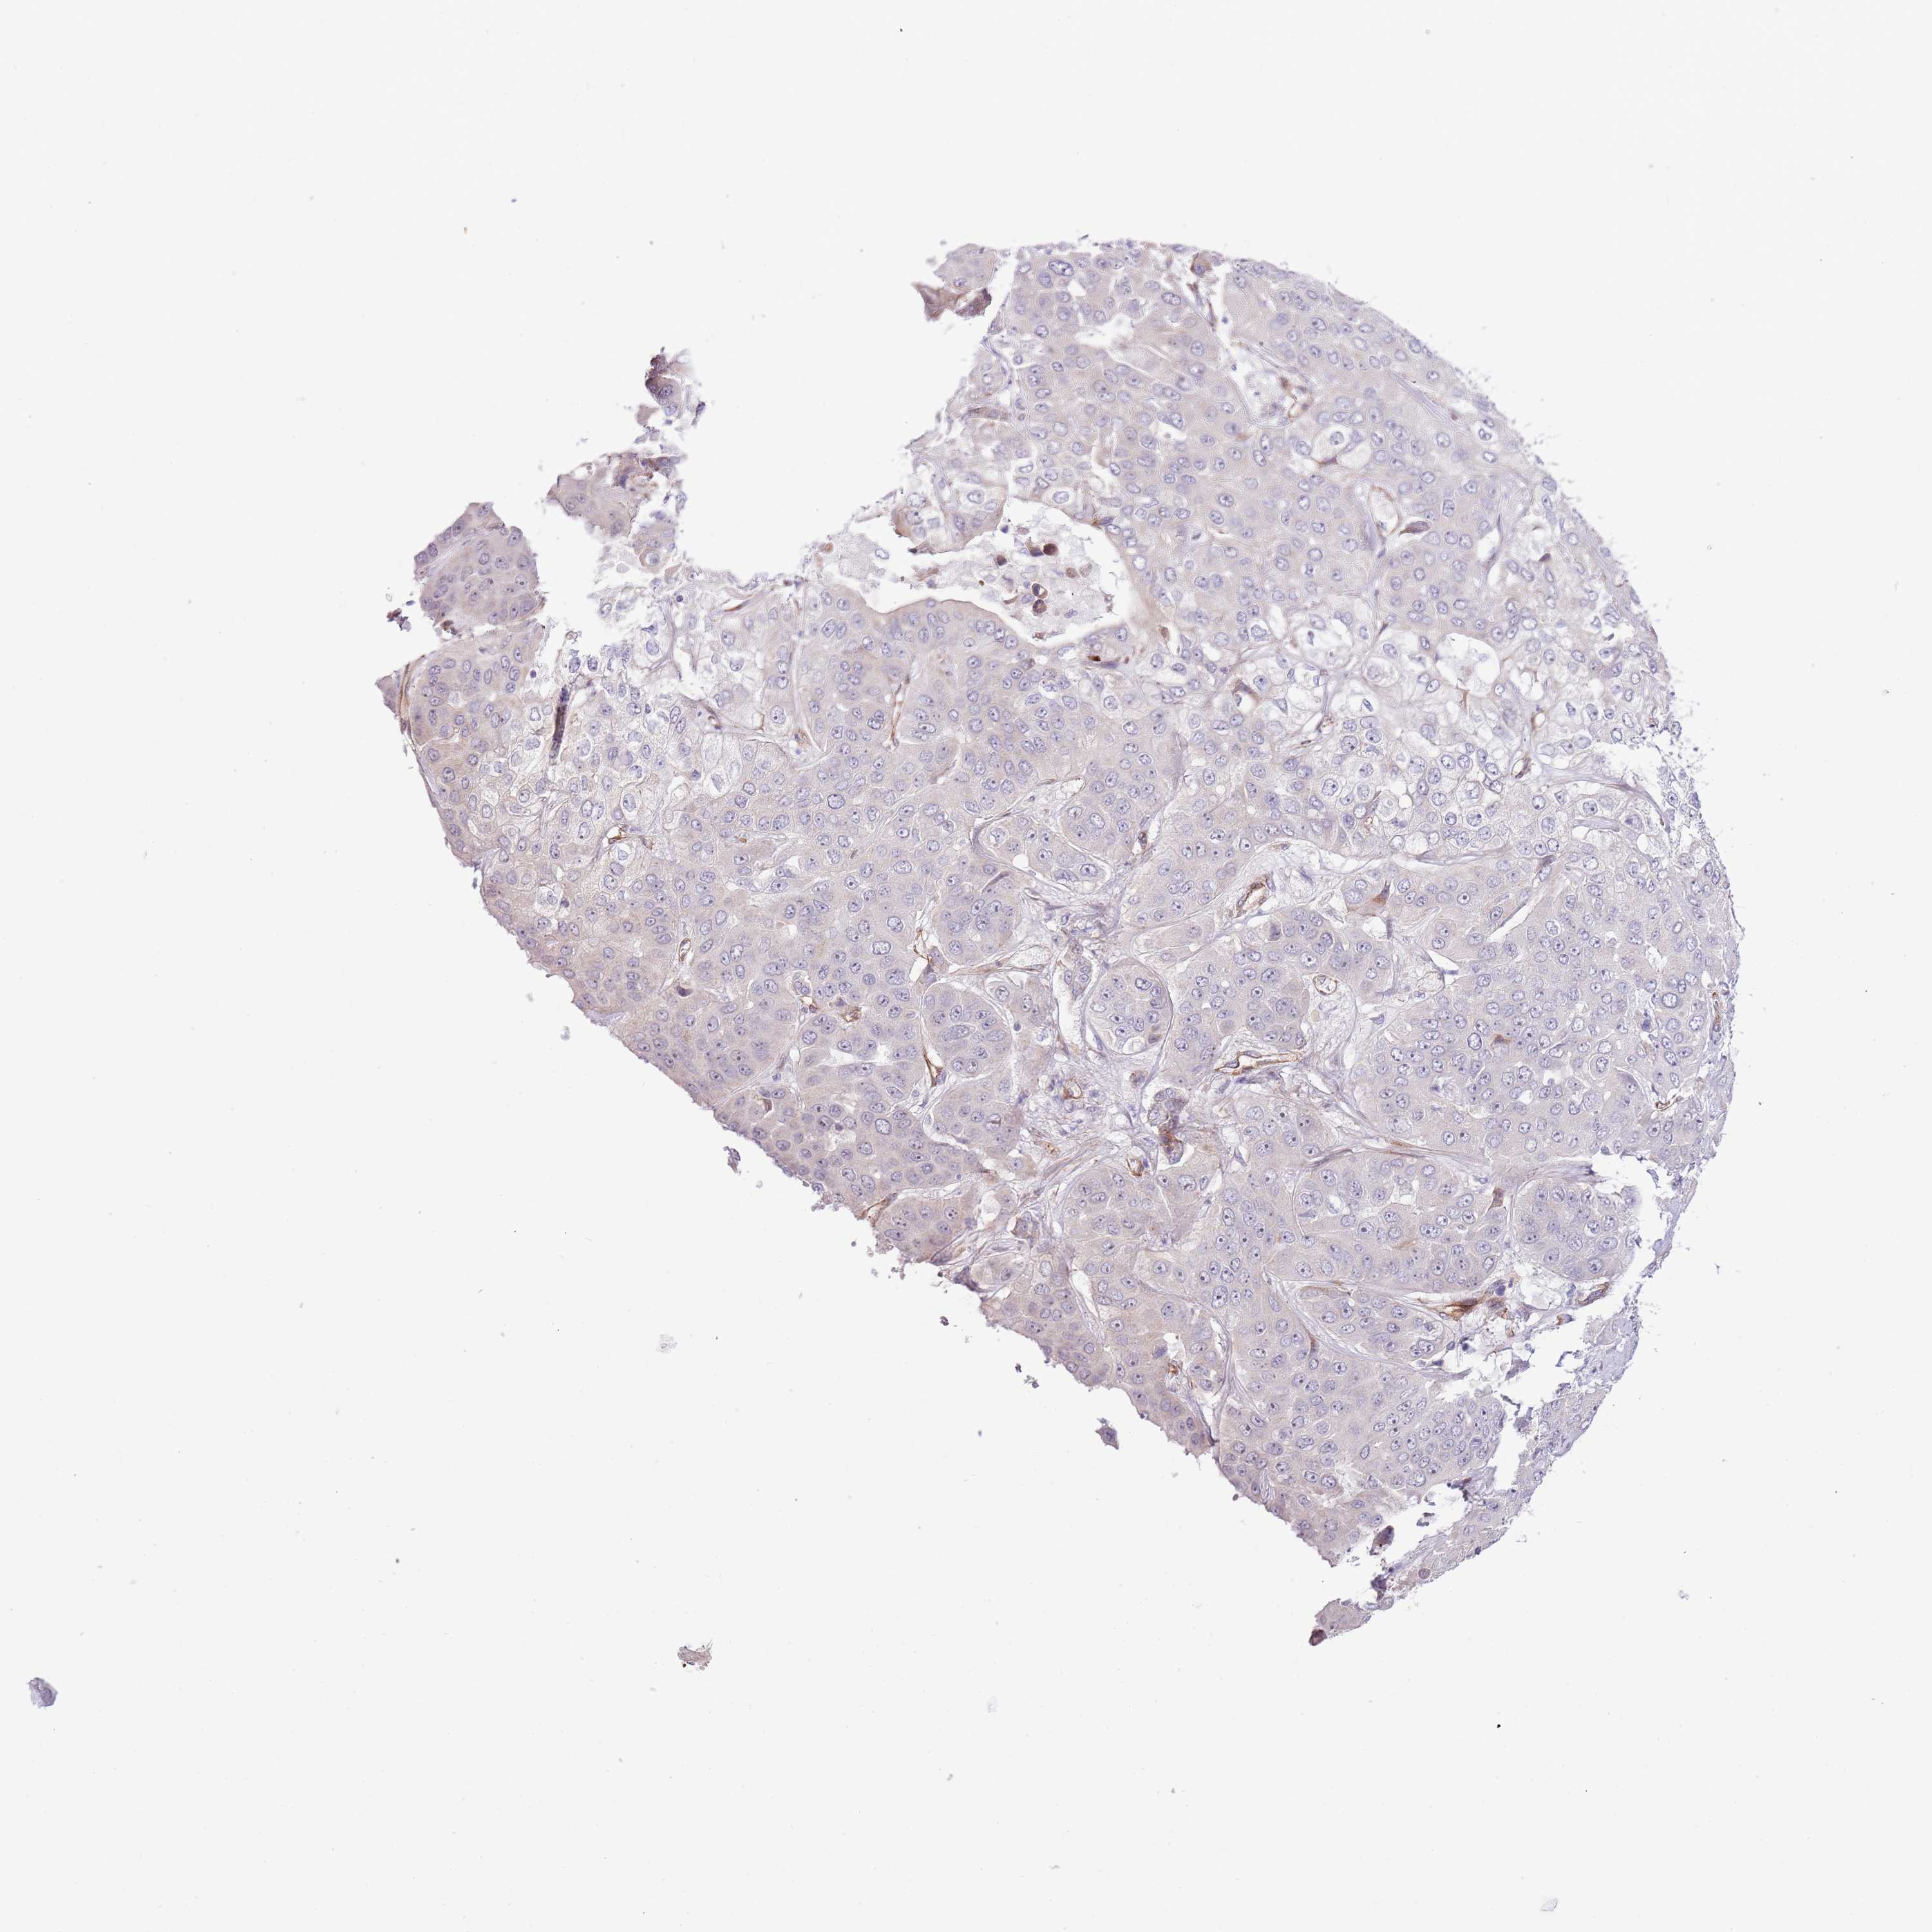

LIVER CANCER - Protein expressioni

A mouse-over function shows sample information and annotation data. Click on an image to view it in a full screen mode. Samples can be filtered based on level of antibody staining by selecting one or several of the following categories: high, medium, low and not detected. The assay and annotation is described here.

Note that samples used for immunohistochemistry by the Human Protein Atlas do not correspond to samples in the TCGA dataset.

Antibody stainingi

Antibody staining in the annotated cell types in the current human tissue is reported as not detected, low, medium, or high, based on conventional immunohistochemistry profiling in selected tissues. This score is based on the combination of the staining intensity and fraction of stained cells.

Each image is clickable and will lead to virtual microscopy that enables deeper exploration of all samples and also displays staining intensity scores, fraction scores and subcellular localization as well as patient and tissue information for each sample.

Antibody HPA019062

Antibody HPA043230

Staining

High

Medium

Low

Not detected

Intensity

Strong

Moderate

Weak

Negative

Quantity

>75%

75%-25%

<25%

None

Location

Nuclear

Cytoplasmic/membranous

Cytoplasmic/membranous,nuclear

Cholangiocarcinoma

Carcinoma, Hepatocellular, NOS